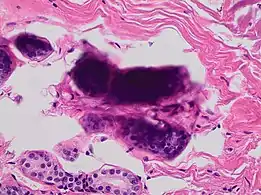

A crush artifact is an artificial elongation and distortion seen in histopathology and cytopathology studies, presumably because of iatrogenic compression of tissues. Distortion can be caused by the slightest compression of tissue and can provide difficulties in diagnosis.[2][3] It may cause chromatin to be squeezed out of nuclei.[4] Inflammatory and tumor cells are most susceptible to crush artifacts.[4]

Crush artifact from compression by forceps on the tissue sample